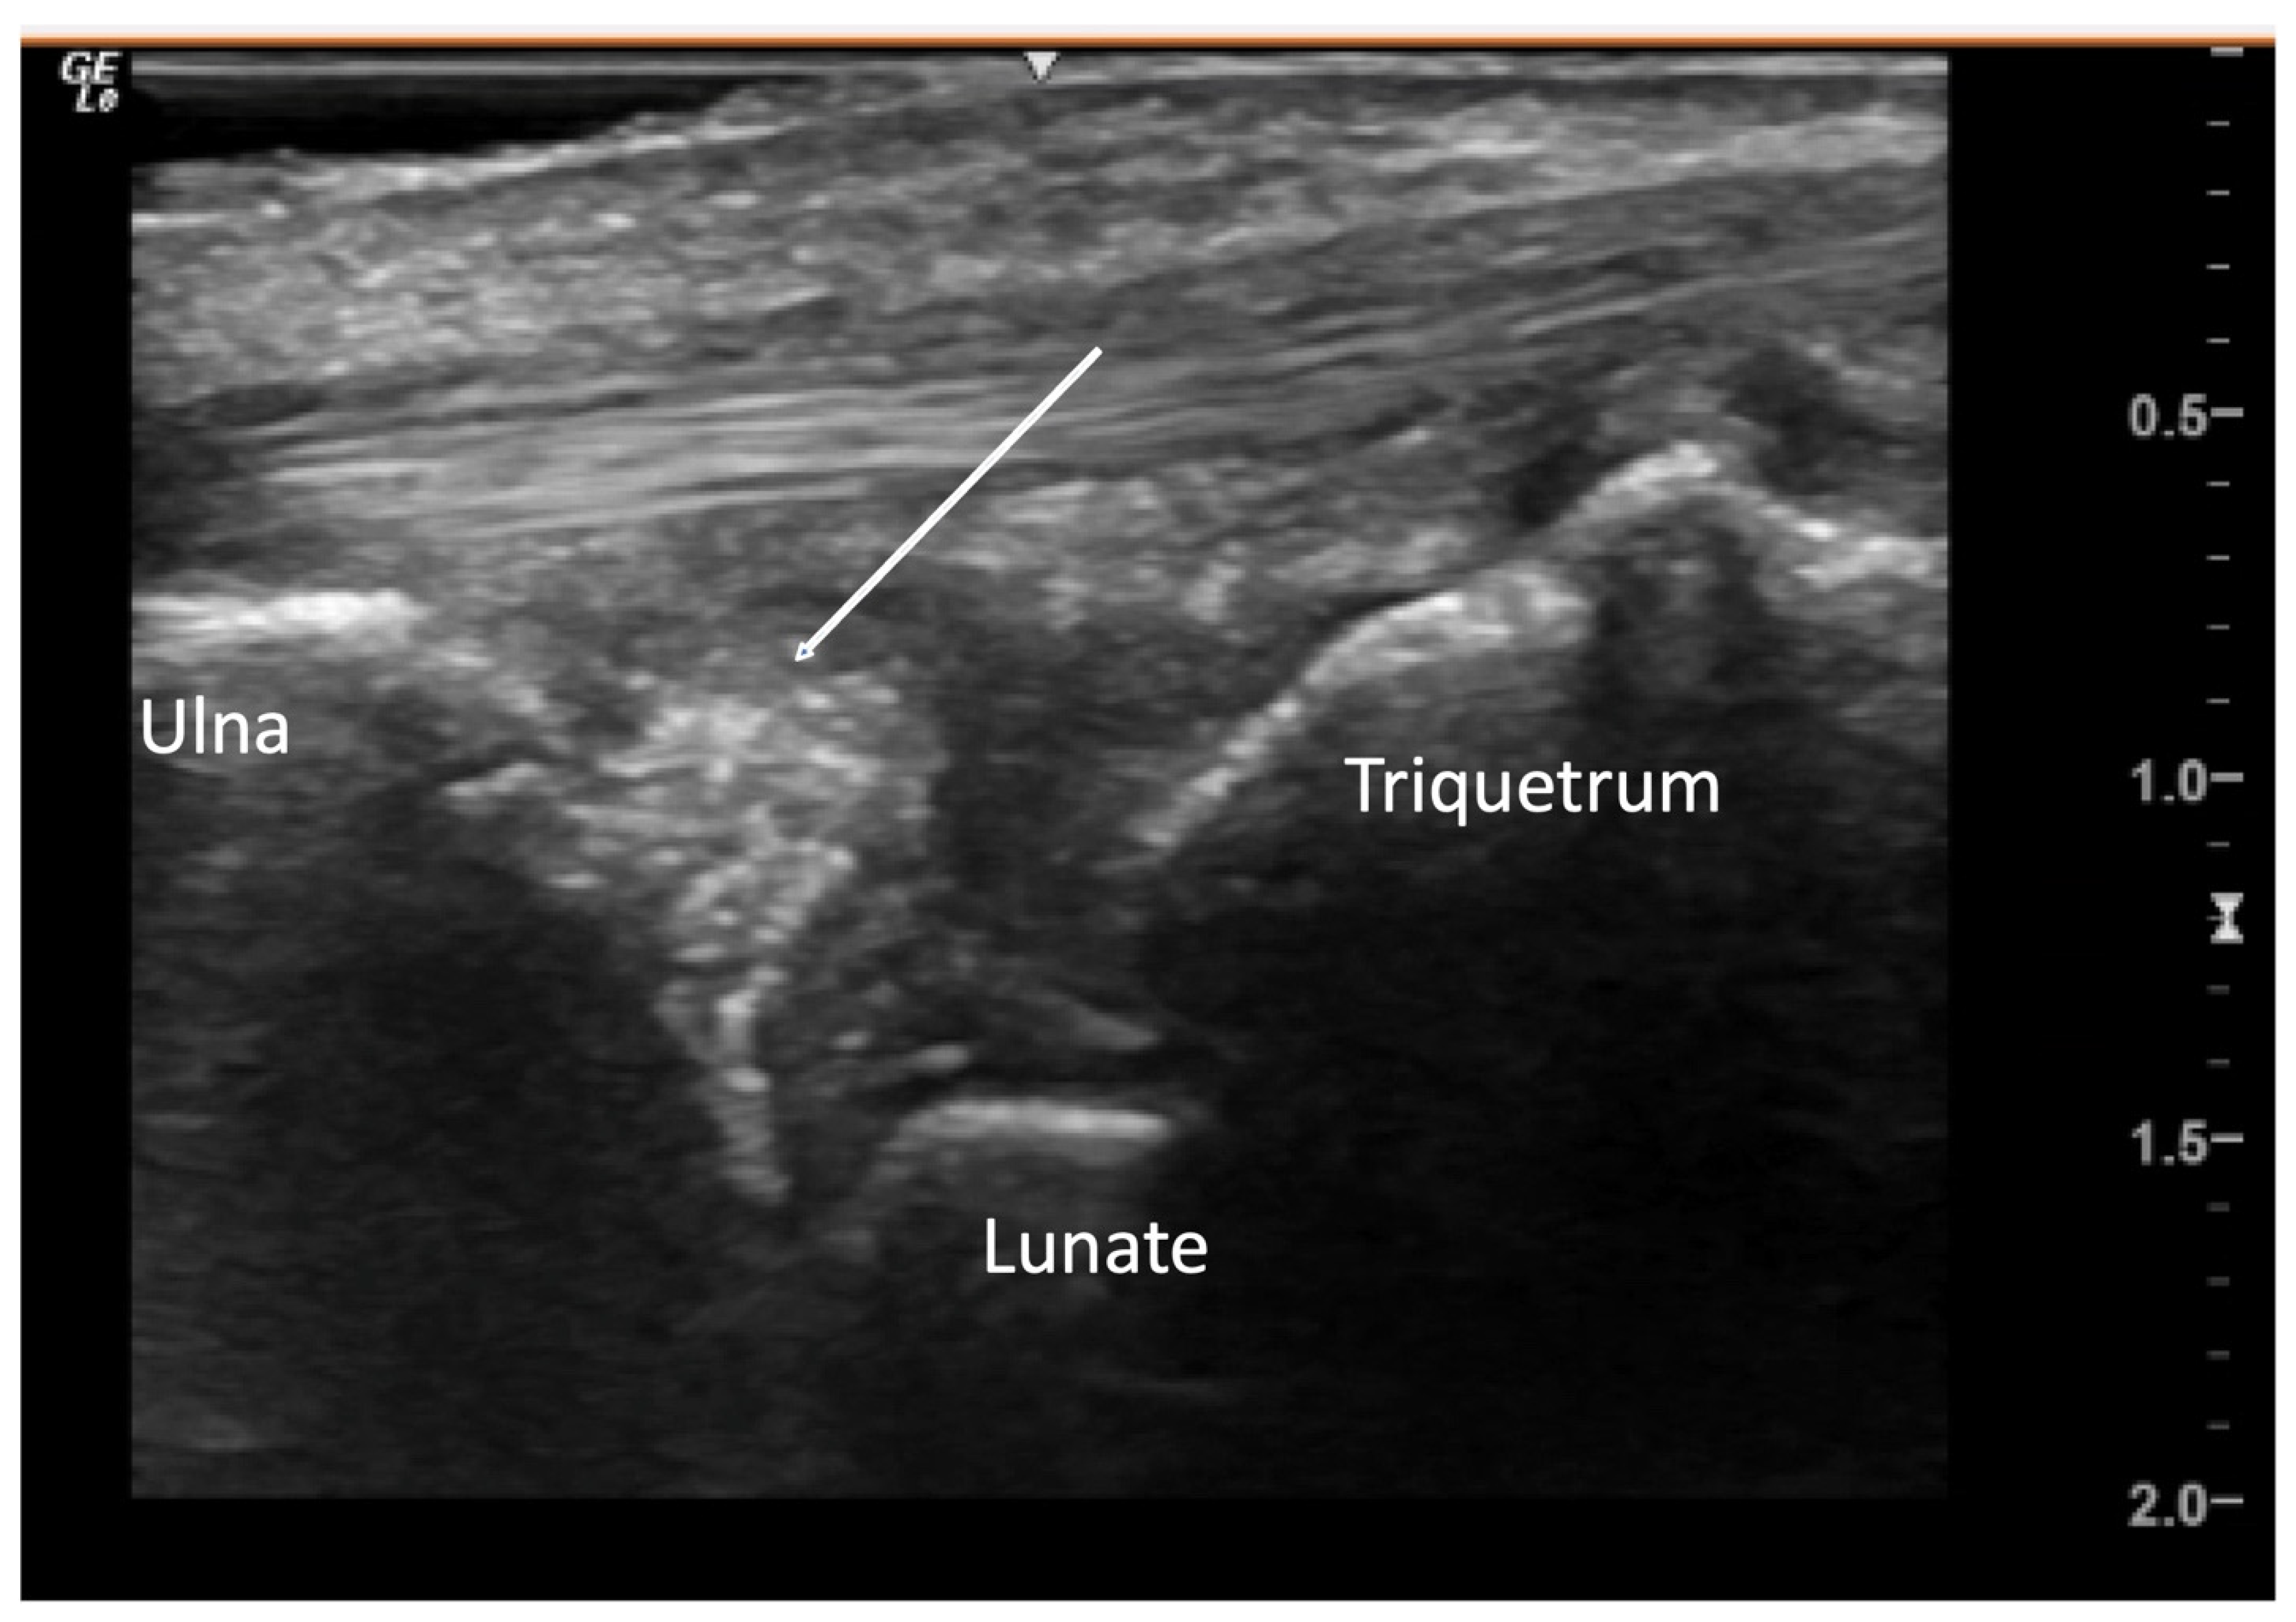

2.1.2. Inflammatory Arthritis

4.1. Evaluation of the Fingers

4.1.1. Dorsal Aspect